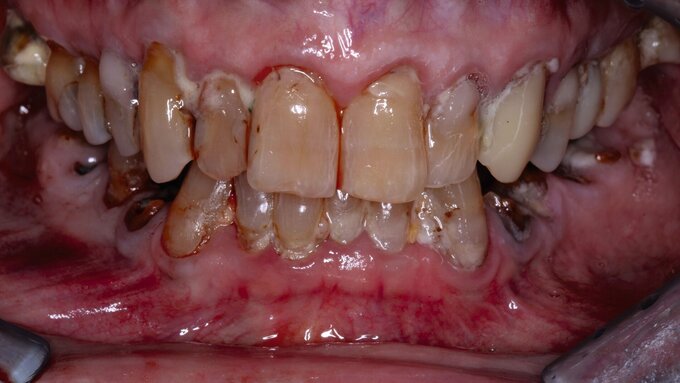

Zudem werden viele ältere Menschen wahrscheinlich mehr eigene Zähne besitzen und möglicherweise höhere Ansprüche bezüglich ihrer Mundgesundheit haben. Damit werden auch die Anforderungen an die Prävention und die therapeutischen Maßnahmen steigen. Auf den ersten Blick scheint es so, dass die zahnärztlichen Maßnahmen bei alten Menschen nicht signifikant von denen bei Jüngeren abweichen – im Detail ergeben sich aber durchaus Unterschiede bezüglich der Behandlungsmöglichkeiten und -maßnahmen: Mit zunehmendem Alter nimmt die Häufigkeit von Krankheiten zu, die zu Mundgesundheitsproblemen führen können. Es ändert sich die Sichtweise bezüglich der Inanspruchnahme zahnmedizinischer Leistungen und die subjektive Wahrnehmung korreliert häufig nicht mehr mit dem objektiven Befund. Außerdem gibt es immer mehr Menschen mit erheblichem Pflegebedarf. In dieser Patientengruppe ist der Karies-Sanierungsgrad wesentlich geringer als bei älteren Seniorinnen und Senioren, die keinen Pflegebedarf haben. Bei der Umsetzung von individuellen Präventionskonzepten ist neben der Etablierung einer altersgerechten Mundhygiene, der Anwendung von Fluoridpräparaten und dem Einsatz unterschiedlicher Biofilm-modifizierender Präparate einer Veränderung der Ernährungsgewohnheiten Aufmerksamkeit zu schenken.

Für die Praxis bedeuten diese Fakten, dass bei Seniorinnen und Senioren ein verstärktes Augenmerk auf Präventivmaßnahmen unter Berücksichtigung der Zunahme freiliegenden Wurzeldentins gerichtet werden muss. Zudem werden vermehrt Austauschrestaurationen erforderlich werden. Da bedingt durch den Abbau des parodontalen Stützgewebes Wurzelkaries-Läsionen zunehmen werden, müssen neue Restaurationskonzepte Eingang in die Praxis finden. Dabei sollte im hohen Alter und bei Patienten mit schlechtem Allgemeinzustand die Erneuerung von Restaurationen mit Augenmaß vorgenommen werden. Vermutlich wird also die Anzahl von Reparaturmaßnahmen zunehmen.

Einer verbesserten Parodontaldiagnostik mit einer Ausweitung der nicht chirurgischen Parodontaltherapie ist bereits mit den neuen Paro-Richtlinien der Weg geebnet worden. Notwendig wird aber auch eine verbesserte Diagnostik und Therapie von nicht-kariösen Zahnhartsubstanzdefekten. Endodontische Maßnahmen werden vermutlich bei Patienten im höheren Lebensalter komplizierter werden und es wird wahrscheinlich eine verstärkte Nachfrage nach Implantaten geben. Gleichzeitig bedeutet dies jedoch auch, dass neben den üblichen Zahnextraktionen vermehrt Implantatentfernungen erforderlich sein werden.